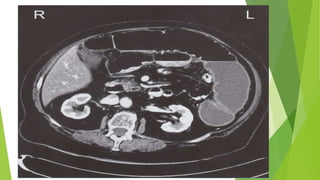

CT abdomen and pelvis with IV contrast

Indications

• Preferred initial imaging modality for suspected diverticulitis

• Diagnostic confirmation in patients with no prior imaging studies

• Staging the severity of diverticulitis

Supportive findings

Colonic outpouching

Signs of inflammation

• Bowel wall thickening > 3 mm

• Peridiverticular mesenteric fat stranding

Complications may also be identified

• Peridiverticular abscess: hypodense collections with peripheral contrast enhancement

• Diverticular perforation: pneumoperitoneum

• Intestinal obstruction: dilated intestinal loops with multiple air-fluid levels